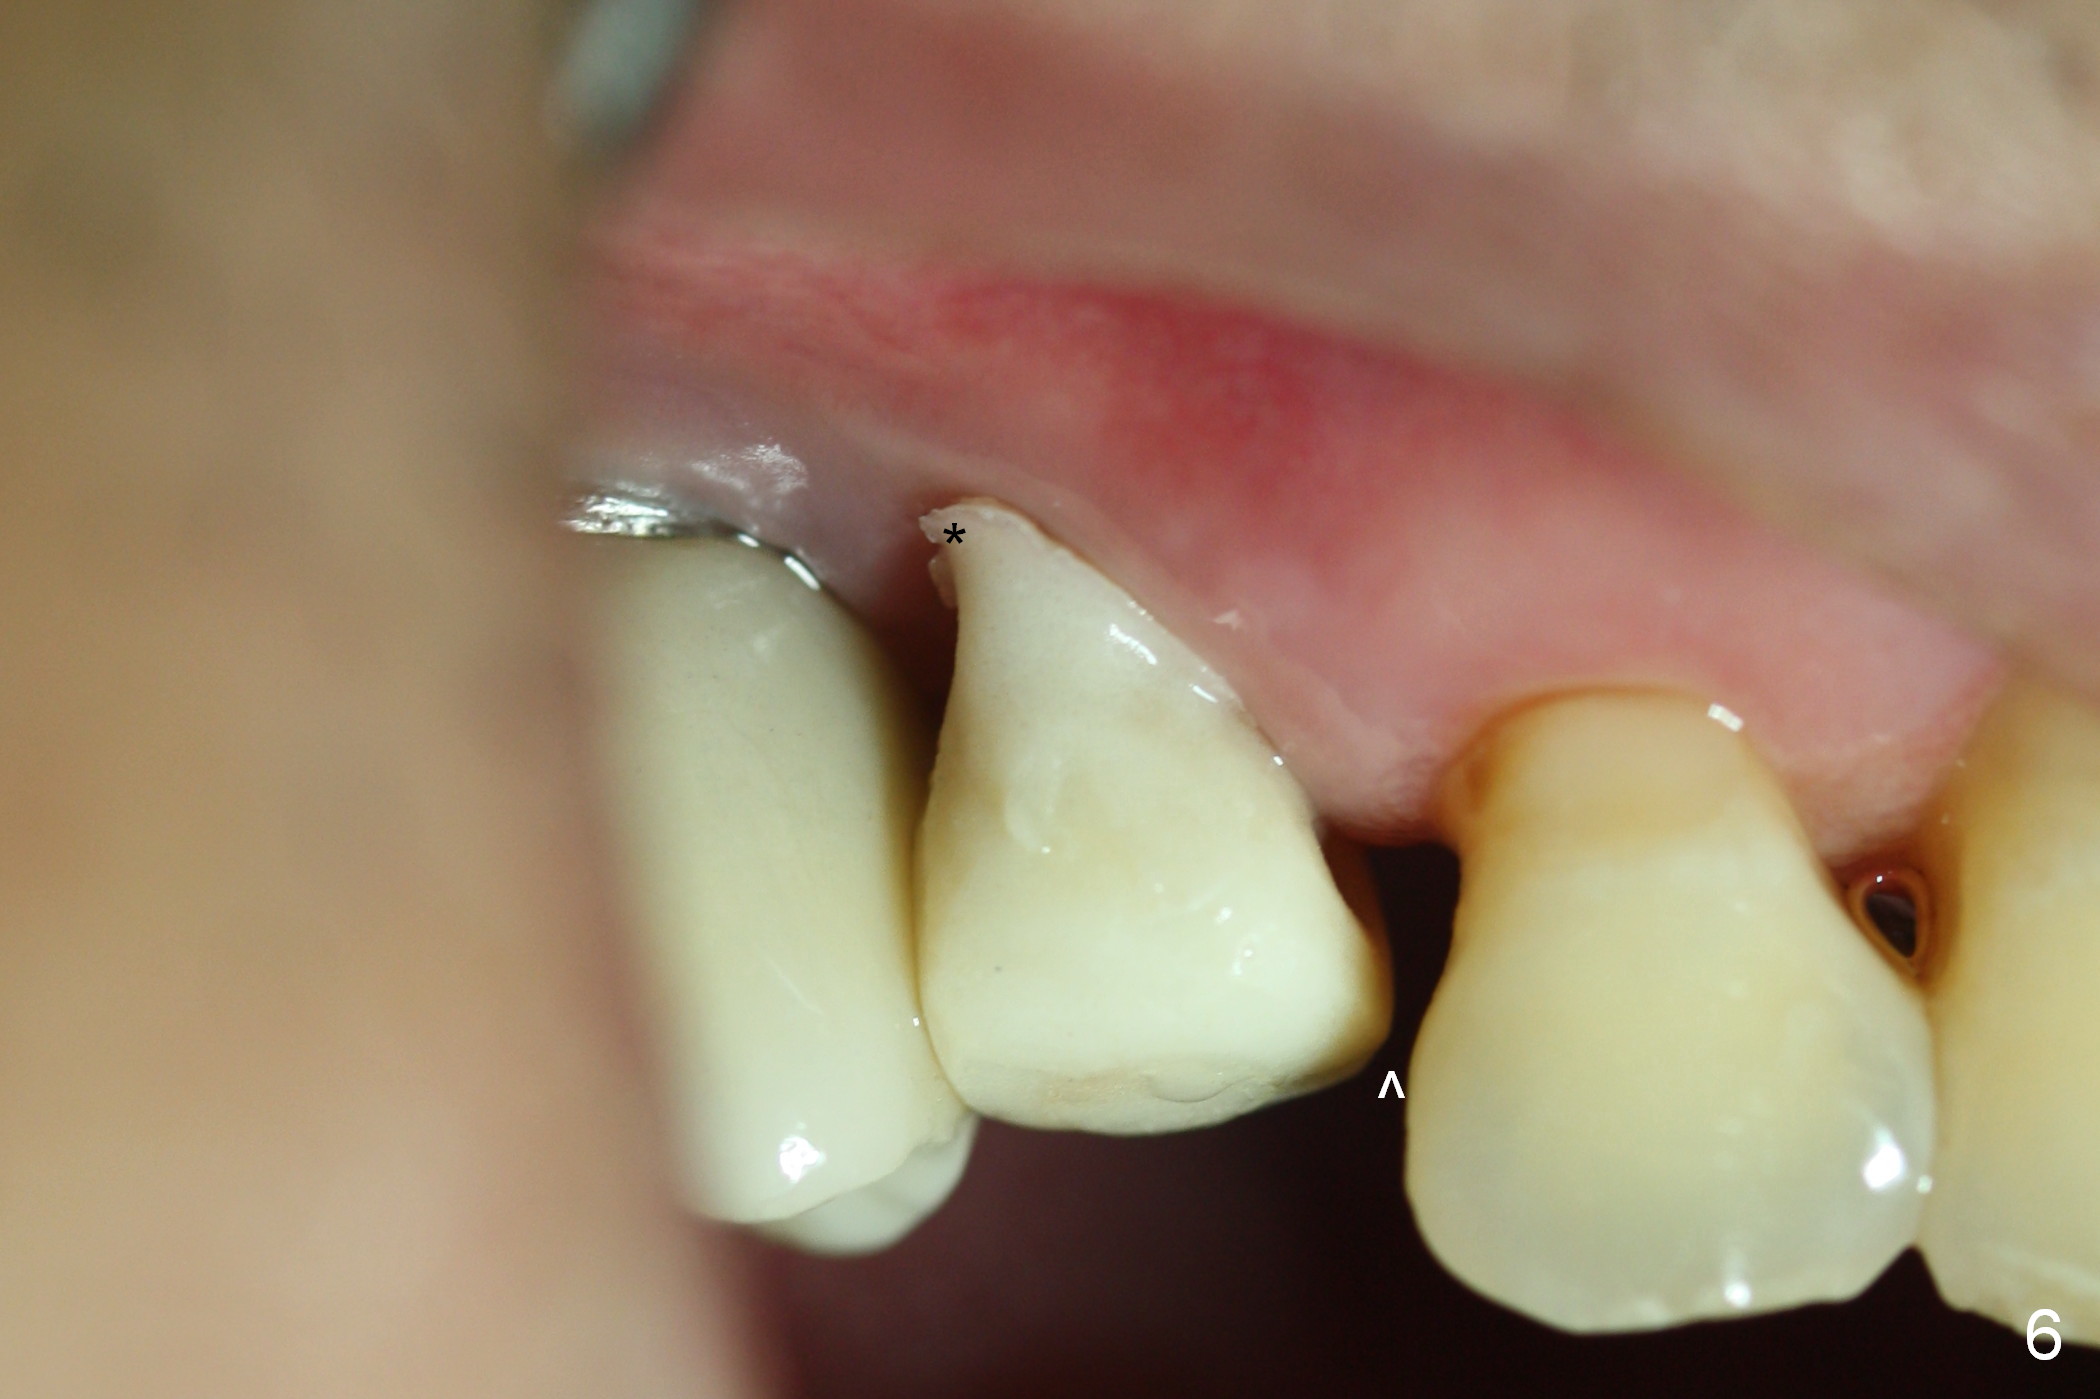

The distal buccal (Fig.1) and palatal (Fig.2) papillae (*) are recessive at the tooth #4.  Following extraction and use of 3.8 mm Magic Drill, a 4.5x13 mm implant is placed lower than the mesial crest (Fig.3) to reduce the chance of the distal implant thread exposure.  The latter is a measure to decrease peri-implantitis.  A 4.5x5.7(4) mm pair abutment is placed (Fig.4,5).  The remaining socket is filled with allograft/Osteogen placement.  The large space between #3 and 4 implants is occupied by the healthy gingiva, where bone graft cannot get in.

Six days postop, the distobuccal margin of the immediate provisional appears to be overbuilt (Fig.6 *).  The overhang was made to cover the distobuccal opening of the socket (Fig.4).  In addition to daily use of water pik, cleaning with .25% Sodium Hypochlorite contributes to the shiny surface of the provisional.  From now on, use cotton pellets soaked with the diluted bleach to clean the provisional and abutment (if exposed) every visit.  For this case, the overhang will be trimmed when the patient returns in 2 weeks so that the distal papilla may grow downward. The mesial contact should be re-established (^).